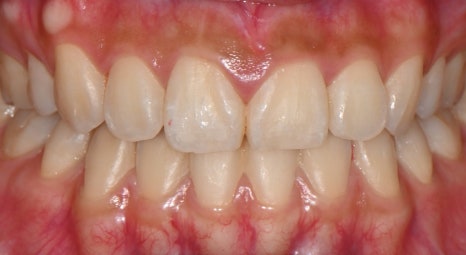

📸 Before

– Dark tooth tone

– Slightly asymmetrical tooth line

📸 After

– Brighter, smoother tooth tone

– Balanced front tooth line

– Natural shaping that harmonizes with the smile line

The patient said, “It’s not that my teeth just look prettier, it feels like my whole face has become brighter,” and shared that for the first time, she smiled widely without holding back when taking photos.